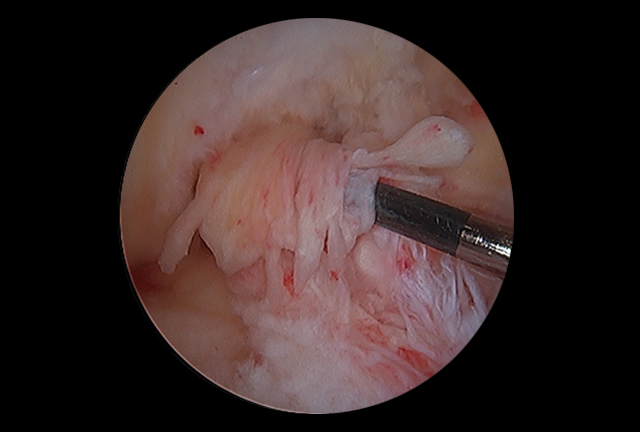

. Arthroscopic Anterior Cruciate Ligament (ACL) Reconstruction

. Meniscal Repair and Cartilage Resurfacing Techniques

There are many controversial choices when it comes to selecting a graft for ACL reconstructive surgery. Though there are other graft options including Hamstring tendons, Quadriceps tendon or Cadaveric tissue, "Autologous" Bone-Patella tendon-Bone is considered the gold standard for high level athletes that participate in twisting, pivoting and deceleration type sports.

In most instances, surgeons will choose a graft type irrespective of a patient’s level of activity. This is usually consistent with a technique learned during their fellowship training, ease of graft harvest (hamstrings) or their desire to use pre-formed cadaveric tissue graft . Having trained in all harvest techniques, I truly believe that autologous Bone-Patella tendon-Bone graft is the graft of choice.

Several studies by the American Journal of Sports Medicine, have confirmed that Hamstring tendon use in ACL reconstructive surgery has a higher incidence of failure, knee joint laxity, infection, arthritis, delayed healing time, graft slippage and hamstring weakness (most noted in deceleration type activities). Although hamstring graft may be considered on occasion in the skeletally immature athlete, it is often considered as a graft option for the low demand, non-contact athlete. The literature also supports that the use of cadaveric tissue in the young high demand athlete has an extremely high failure rate.

Upon review of surgeon's graft choices throughout the nation, more than 75% of surgeons utilize autologous Bone-Patella tendon-Bone grafts during ACL reconstructive procedures in professional and/or collegiate athletes. This graft has been described as having a lower incidence of failure, better fixation, quicker incorporation into bone and the highest rate of return to full pre-injury activities, including sports.

Over the last 20 years, I have used Bone-Patella tendon-Bone in the majority of my high level athletes. There has been no reported weakness subsequent to harvesting this graft type. Although prior literature describes that this technique may predispose a patient to occasional anterior knee pain and/or tendinitis, with careful graft harvest, bone grafting to the patella defect and repair of the patella tendon site, these postoperative symptoms have become negligible.

It is true that surgeon experience, state-of-the-art anatomic technique and proper fixation/ tensioning methods have a significant bearing on the results of this procedure; but there is also enough evidence supporting that proper graft choice significantly contributes to the athletes’ ability to return to sports at a competitive level with excellent long-term results.